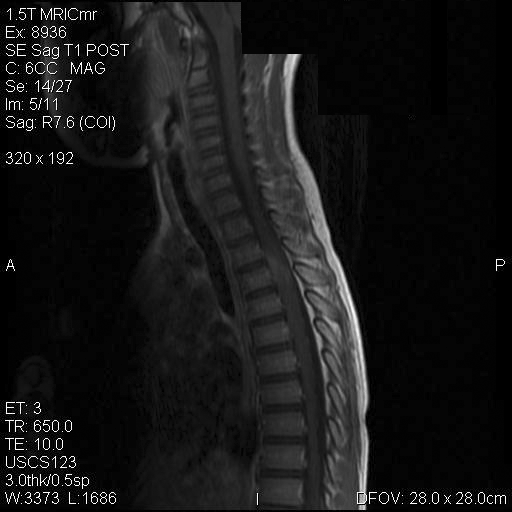

Representative images from the MR studies and specimen are illustrated below:

A. T1 |

B. T1+Contrast |

C. T1+Contrast |

D. T2 |

E. T1+Contrast |

Panel A to E are MR images. Panel F and G are taken from intraoperative cytologic preparation. Panel H to M are taken from frozen section. Panel N and O are from paraffin section. These sections are stained by hematoxylin-eosin stain. Panel P is immunohistochemistry for neurofilament proteins. Panel Q is stained by Luxol fast blue-Periodic acid Schiff (LFB-PAS) stain.

MR Imaging:

The segment of spinal cord at T3-T4 level is expanded and is accompanied by edema that runs from T2-T6. The expansion and edema is roughly symmetrical along the long axis of the cord. The expanded levels are isointense to the white matter of the spinal cord on T1-weighed images (Panel A). The edema is best demonstrated on T-weighed images (Panel B, C, and E). Patchy and poorly defined enhancement is demonstrated in the expanded areas (Panel D). The remaining levels of the spinal cord and the brain are free of abnormal changes.